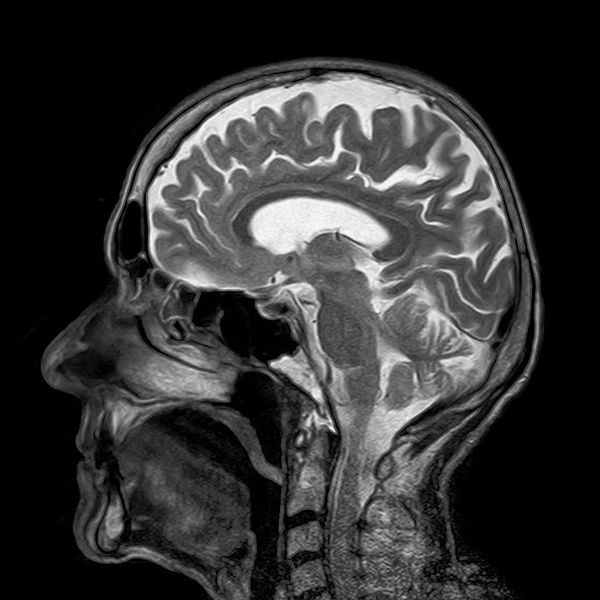

**核磁共振图像(图源:pixabay.com)**

CT同样有一个非常突出的缺点:它的辐射性非常强。这似乎是个死结:不用CT,看不到患者身上的病变;运用CT,多少会有一点辐射,用多了,也有可能损害健康。

2003年的诺贝尔生理或医学奖,便颁发给了解决这个问题的人:保罗·劳特伯(Paul Lauterbur),化学家;彼得·曼斯菲尔德(Peter Mansfield),物理学家。

正常的生理反应、正常的细胞,各种疾病的发生、演变,都离不开水分。劳特伯发现,水分子里的氢原子核,具有磁性。正常情况下,氢原子核们彼此聚集,磁性互相抵消。如果的施加一个较强的磁场,便如同往铁粉中放入一块磁铁,氢原子会在磁力的作用下乖乖排队。随后,曼斯菲尔德进一步发现,如果在此时加入一个脉冲,不同位置的氢原子会显现出不同的变化,而这种变化,可以被测量。

经两位大神之手,便诞生另一种极其常见的设备:核磁共振机(MRI)。比之于CT,MRI有两个优点......